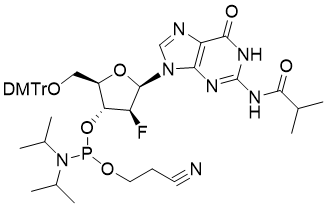

馬鞍山致研生物醫(yī)藥科技有限公司成立于馬鞍山市鄭浦港新區(qū)現(xiàn)代產(chǎn)業(yè)園。公司專(zhuān)注于生物小分子、醫(yī)藥中間體相關(guān)產(chǎn)品的研發(fā)和生產(chǎn),產(chǎn)品主要包括DNA亞磷酰胺單體、RNA亞磷酰胺單體、特殊單體以及按照客戶(hù)要求定制的RNA和DNA,并且公司提供定制合成等方面的研究服...

馬鞍山致研生物醫(yī)藥科技有限公司成立于馬鞍山市鄭浦港新區(qū)現(xiàn)代產(chǎn)業(yè)園。公司專(zhuān)注于生物小分子、醫(yī)藥中間體相關(guān)產(chǎn)品的研發(fā)和生產(chǎn),產(chǎn)品主要包括DNA亞磷酰胺單體、RNA亞磷酰胺單體、特殊單體以及按照客戶(hù)要求定制的RNA和DNA,并且公司提供定制合成等方面的研究服...